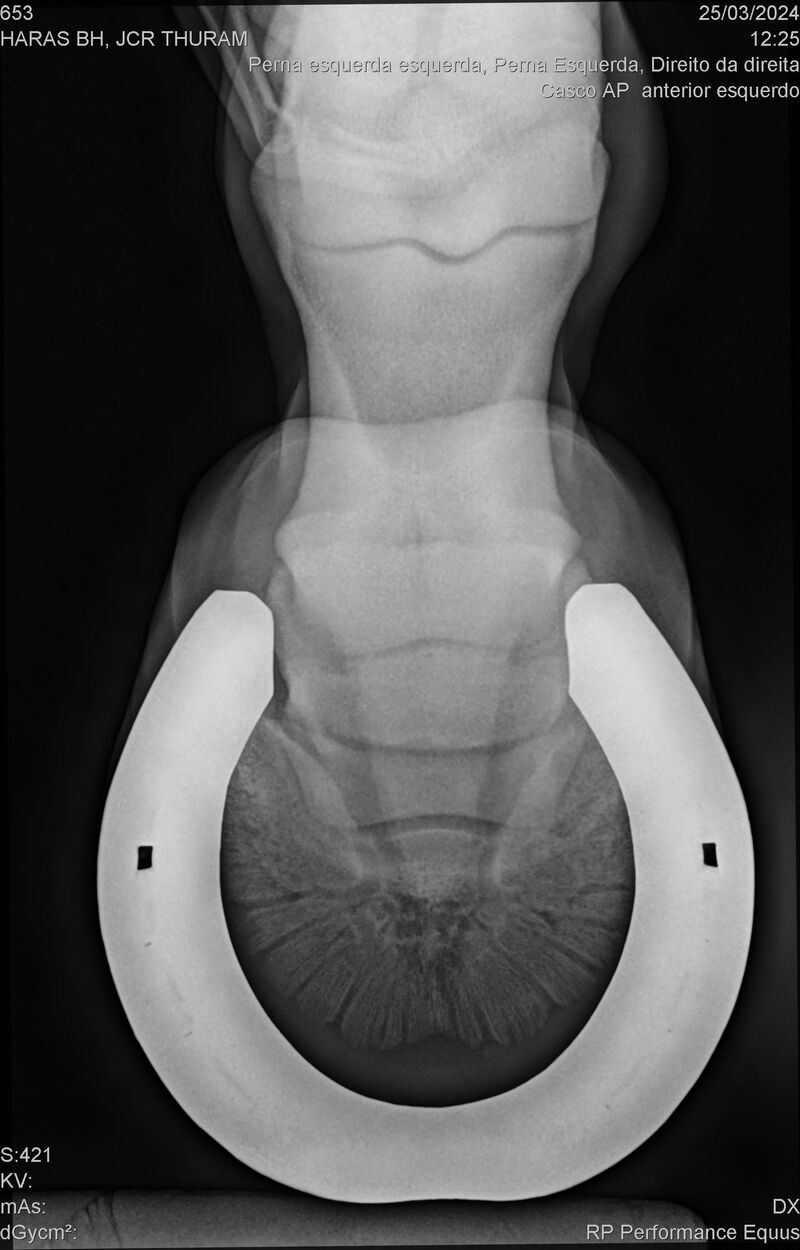

JCR THURAM

Raça: BRASILEIRO DE HIPISMO

Sexo: CASTRADO - CASTRADO

Nascimento: 10/01/2021

Altura Aproximada: 1,58

Pel.: CASTANHO

Registro: 27531-BH

Vend.: HARAS BH

Local : VINHEDO/SP